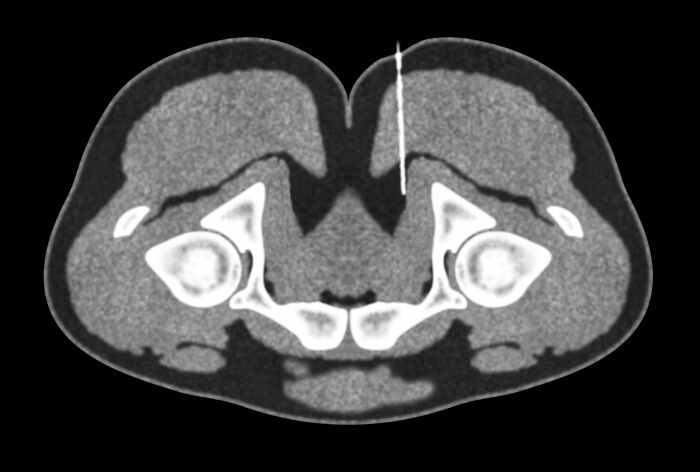

#18

When you get a kidney transplant, they leave the old one in there and stick the new one in your pelvis. There are people walking around with three or four kidneys.

Jennacyde153:

My colleague’s dad just got 2 new ones so now he has 4. My kid only has 1 kidney but it’s as big as an adult kidney.

© Photo: common_sensei